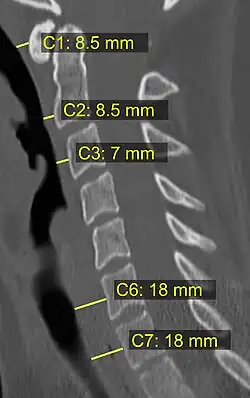

On CT scan or X-ray, a cervical fracture may be directly visualized. In addition, indirect signs of injury by the vertebral column are incongruities of the vertebral lines,[7] and/or increased thickness of the prevertebral space:[8]

![CT scan with upper limits of the thickness of the prevertebral space at different levels[8]](./_assets_/CT_of_prevertebral_space.jpg)